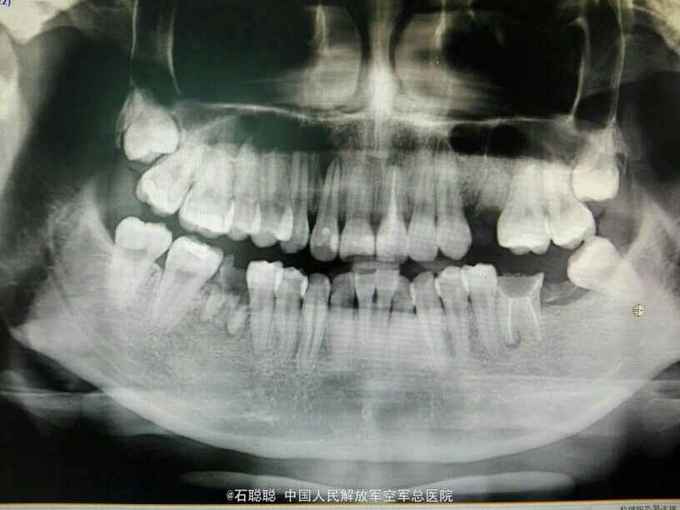

检查:21牙体变色,切缘磨耗不均匀,舍面见牙色充填体完整在位,无松动,叩痛-,牙龈未见明显异常。 根尖片:21根管内高密度充填影像,恰填;12根尖远中见直径约3mm低密度透射影像 曲面断层:36、46残根,根尖低密度影